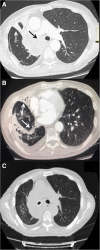

Background: Tracheobronchial malignant stenosis is a life-threatening condition which may cause recurrent infections due to lung atelectasis. Despite immunotherapy is less toxic than standard chemotherapy, recurrent lung infections may represent a challenge for this treatment. We report a clinical case of a patient with metastatic squamous cell carcinoma suffering from pulmonary infections due to central airway obstruction who underwent endoscopic recanalization followed by immunotherapy. VSports手机版.

Case presentation: A 64 year-old man was referred to our attention for the management of metastatic squamous cell carcinoma obstructing the right main bronchus with recurrent pulmonary infections. Patient exhibited strong positive PD-L1 expression (> 50%) V体育安卓版. Advanced disease stage contraindicated surgical treatment. Although therapy with immune check point inhibitors was indicated as first-line treatment, recurrent pulmonary infections made it unfeasible. Therefore, we planned a combined approach including endoscopic recanalization of central airway in order to resolve lung atelectasis, and lung infection followed by immunotherapy treatment with pembrolizumab in order to avoid local and systemic disease progression. .

Conclusions: At 16-week follow-up, the patient was alive in stable disease with improvement of clinical condition and no signs of lung infection. V体育ios版.